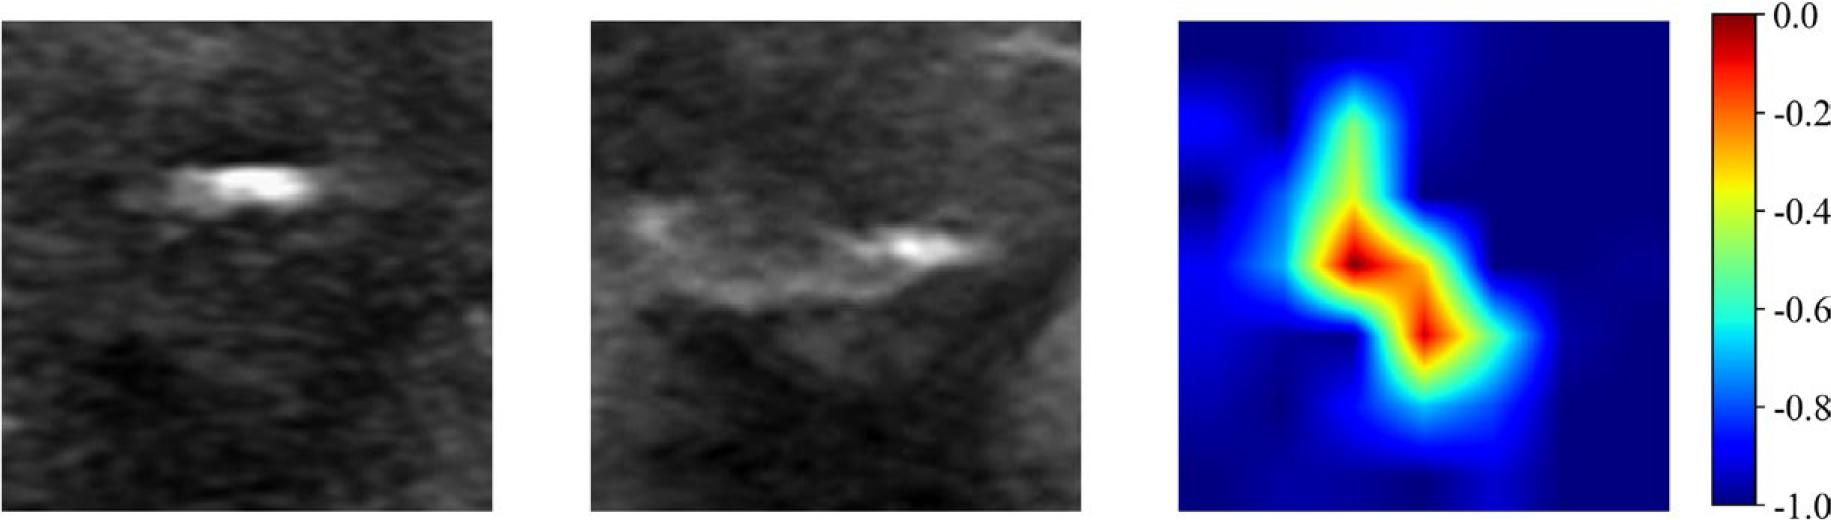

In both the training and validation sets, the AUC values of Model 3: DL_F were 0.765 (95% confidence interval [CI]: 0.703 - 0.826) and 0.723 (95% CI: 0.617 - 0.828), respectively. These values were significantly higher than those of Model 1: DL_L (0.673 [95% CI: 0.603 - 0.742] and 0.671 [95% CI: 0.563 - 0.779], P = 0.049, 0.019) and Model 2: DL_C (0.618 [95% CI: 0.542 - 0.693] and 0.542 [95% CI: 0.426 - 0.658], P = 0.002, 0.042). In the external test set, the AUC value of Model 3 was 0.726 (95% CI: 0.574–0.878), which was also higher than the AUC values of Model 1 (0.547 [95% CI: 0.400-0.691]) and Model 2 (0.510 [95% CI: 0.359-0.662], P = 0.043, 0.049). Additionally, gradient-weighted class activation mapping (Grad-CAM) was used to perform an interpretability analysis of Model 3 (Figure 3).

Gradient-weighted Class Activation Mapping images predicted by the dual-channel deep learning model. The left image represents the minimum bounding rectangle containing the largest section of the tumor on the longitudinal section. The middle image represents the minimum bounding rectangle containing the largest section of the tumor on the transverse section. The right image represents the Gradient-weighted Class Activation Mapping image.